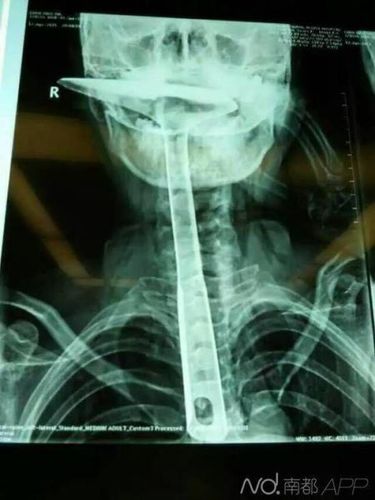

女子因喉咙难受将30公分炒菜锅铲插进食道

炒菜用的锅铲长达30公分,活生生插进自己的食道。

南都讯 记者肖佩佩 炒菜用的锅铲,长达30公分,活生生插进自己的食道,只剩下铲勺露在嘴巴外面,整个食道严重受损。医生都不禁感叹:“这真的是50年难遇的病例。”

近日,康华医院就为这么一位来自虎门的女性患者进行了急救手术,医生细问原因后也是惊呆了,“患者自称,做饭时突然呼吸困难,仿佛喉咙里长了一个大疱,想到当地有土方法,拿东西通一通就好了。”

目前,患者已经历了两期手术,再过两周就要出院了。“但是,患者胸位食道损伤严重,25公分的食道已切除了20公分。”